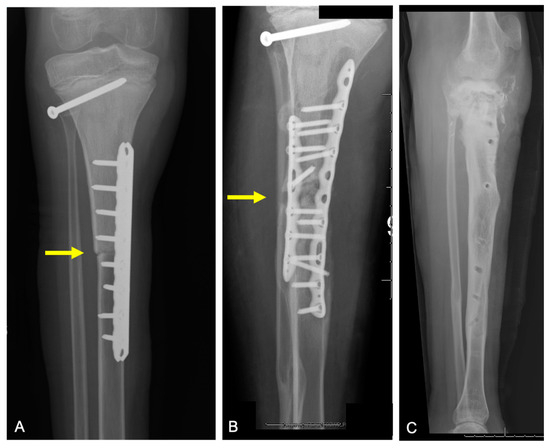

2.2.2. Graft–Host Nonunion

2.3.2. Structural Failure of Allografts